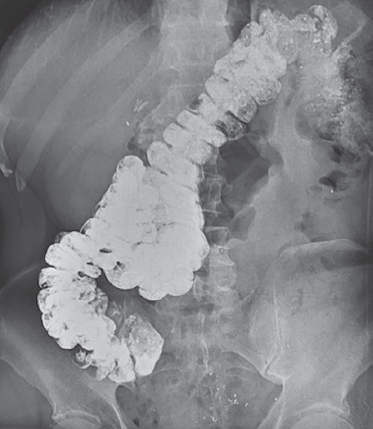

В связи с выраженными запорами и болями в правой половине живота пациенту произведена пероральная ирригография в положении лежа и стоя. На ирригограмме, выполненной через 24 ч после приема бариевой взвеси в положении лежа, установлена причина запоров и болей в правой половине живота — сращение восходящей и начального отдела поперечной ободочных кишки по типу «двустволки» протяженностью 10 см, приводящее к выраженному замедлению транзита кишечного содержимого (рис. 2).

Рис. 2. Пациент З., 68 лет. Пероральная ирригограмма в положении лежа. Визуализируется спаечная деформация ободочной кишки

Fig. 2. Patient Z., age 68. Oral irygography in position lying down. The adhesive deformity of the colon is visualized

На ирригограмме, выполненной в положении стоя, выявлено опущение правого отдела ободочной кишки и медиальное смещение проксимального отдела восходящей кишки, обусловленное давлением патологически подвижной печени (рис. 3).

Рис. 3. Пациент З., 68 лет. Пероральная ирригограмма в положении стоя. Визуализируется опущение правого края печени

Fig. 3. Patient Z., age 68. Oral irygography in position standing up. Visualization of the descent of the right edge of the liver